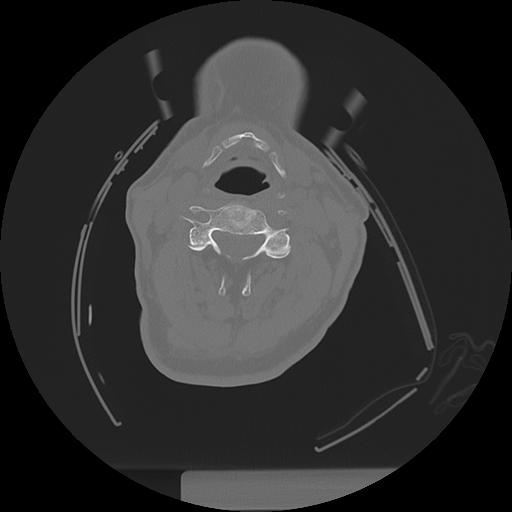

11 HUESO,,Axial,2.0,HUESO,,